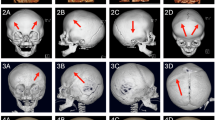

At 6 months of age, his body weight, length, and OFC were 7645 g (25th–50th percentile), 68.8 cm (50th–75th percentile), and 43.0 cm (25th–50th percentile), respectively. He showed distinctive features, including prominent forehead, arched eyebrows, midface hypoplasia, thin upper lip, small mouth, long philtrum, retrognathia, and low-set ears (Fig. 1a–d). No abnormal findings were observed in the chest or abdomen. Neurological examination revealed hypotonia with scarf signs. There were no abnormal data in routine blood examinations, including liver function, thyroid function, lactate/pyruvate, and amino acid profiles. Metabolomic analysis of urine also showed normal results. Conventional chromosomal G-banding revealed a normal male karyotype (46,XY). Skull 3D-computed tomography (CT) images at 10 months revealed partial early fusion of the sagittal and lambda sutures (Fig. 1e). Surgical cranioplasty was performed twice, at 12 and 18 months. Brain magnetic resonance imaging (MRI) at 11 months showed a slightly reduced volume of the cerebrum but no abnormal signals (Fig. 1f, g).

Facial appearance of the patient at 6 months of age (a, b) and 5 years of age (c, d), suggesting deformity of the skull, forehead protrusion, arched eyebrows, flat nose base, thin upper lip, small mouth, long philtrum, retrognathia and low-set ears. e 3-dimensional CT image of the skull at 10 months of age shows partial early fusion of the sagittal and lambda sutures (arrows). T1-(f) and T2-(g)-weighted brain MRI at 11 months of age showed no apparent abnormalities.